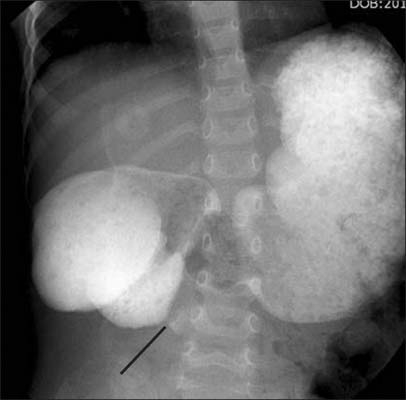

Fig. 1

Simple X-ray shows severe dilated stomach and duodednum 1st portion.

Fig. 1 Simple X-ray shows severe dilated stomach and duodednum 1st portion.